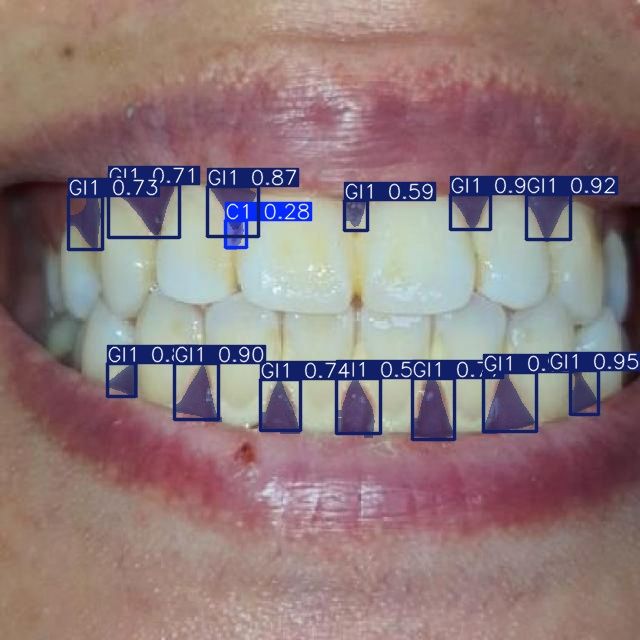

Мы проводим discovery-фазу для нашего клиента (стоматологическая клиника в Москве) и создали работающий прототип ИИ-сервиса, который автоматически сегментирует зубы и связанные патологии по 10 специализированным классам на стоматологических изображениях. Решение построено на Ultralytics YOLOv11-seg, обучено на пользовательском датасете и ускоряется на GPU (CUDA). Прототип уже демонстрирует корректную сегментацию и классификацию по классам кариеса, состояниям десен и показателям пародонта, что открывает путь к автоматизированной диагностике, системам поддержки клинических решений и оценке состояния зубов в реальном времени.

Достигли точной классификации по 10 различным категориям зубов:

- Кариес: C1, C2, C3

- Состояние десен: G1

- Воспаление десен (гингивит): GI1, GI2, GI3

- Пародонтальные индексы: PDI1, PDI2, PDI3